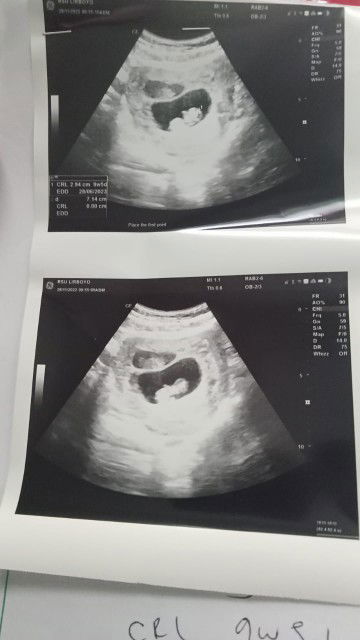

HPL JUNI 2023